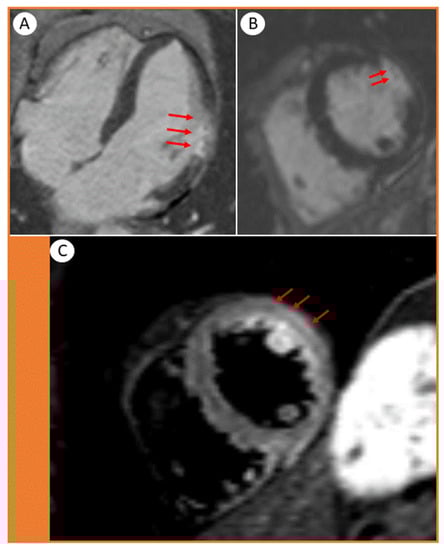

Next, we performed a cardiac magnetic resonance (CMR), which showed transmural late gadolinium enhancement (LGE) in the mid-ventricular level of the lateral wall, involving the papillary muscle (Figure 3A–C, arrows).

The findings were strongly suggestive of a transmural myocardial infarction/necrosis. The damaged area fitted well with obstruction in a minor myocardial branch of the LCx, most likely by a microthrombus (Figure 3B, arrows). The presence of edema in the same segments (Figure 3C, arrows) suggested that the infarction was relatively recent, also supported by the typical rise and fall pattern of cardiac troponins.

Figure 3. Cardiac magnetic resonance images showing (A) 4-chamber and (B,C) short axis views. The transmural distribution of late gadolinium enhancement (LGE) in the lateral wall of the left ventricle displays the extent of the infarction. (B, arrows) Microvascular obstructions are presented as tiny spots within the LGE. (C, arrows) The short-axis STIR acquisition shows edema in the lateral wall and papillary muscle.

The thrombi may be difficult to detect clinically. In our case, the global LV ejection fraction was normal, and the hypokinetic segment in the lateral wall was hardly appreciable. However, speckle tracking echocardiography, a more sensitive method for assessing subclinical myocardial dysfunction, showed segmental strain impairment and raised the suspicion of underlying myocardial injury in a minor area within the lateral wall. CMR is an excellent imaging modality to differentiate between myocarditis-like injury, acute myocardial infarctions and stress-cardiomyopathy [9]. In our case, the late gadolinium enhancement (LGE) features on CMR confirmed the pattern, exact localization (involving a small transmural branch) and extent of the acute cardiac injury. The transmural LGE appearance suggested acute myocardial infarction rather than myocarditis.